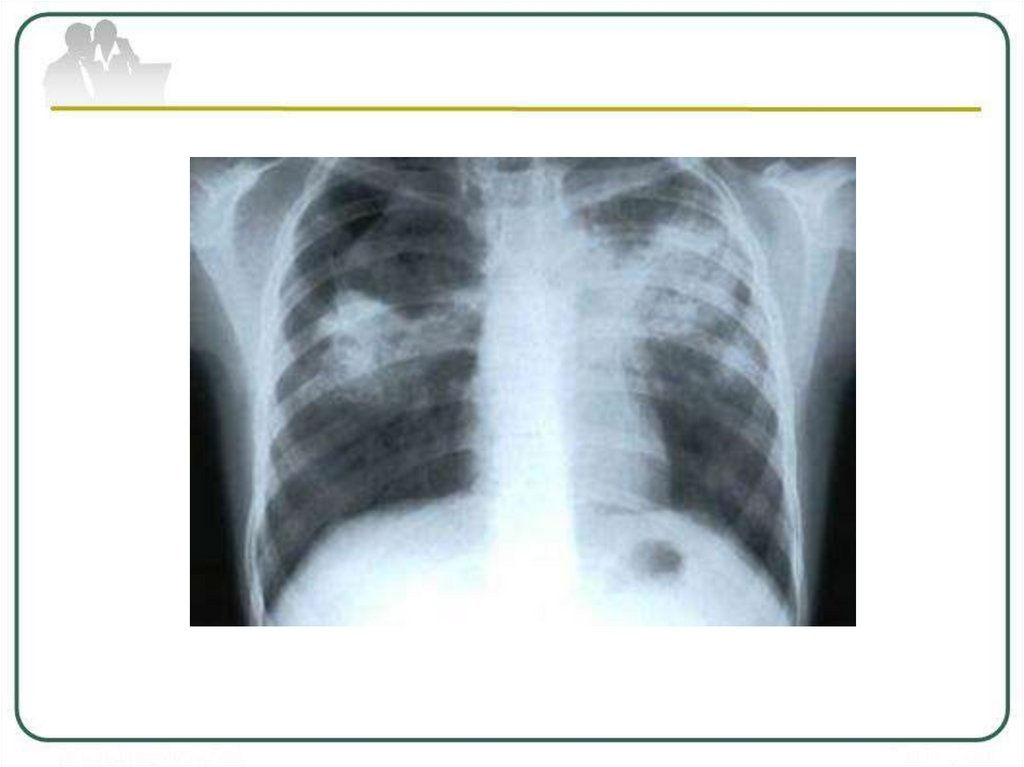

Очаговый и инфильтративный туберкулез презентация - 94 фото